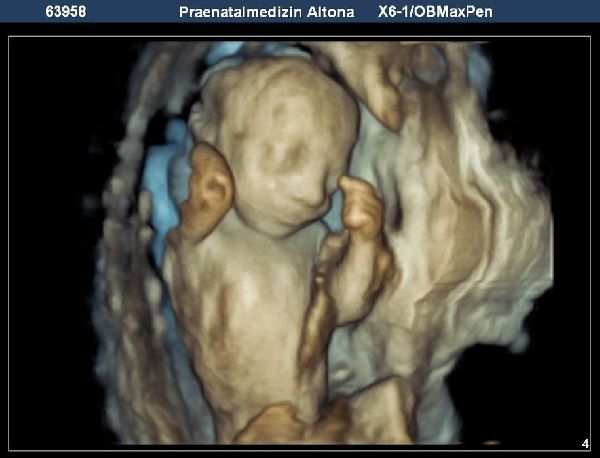

In der Pränatalen Diagnostik bieten wir alle Verfahren mit High-End-Geräten der neuesten Generation an: Ersttrimesterschall, Fehlbildungsschall, fetale Echokardiographie, Dopplersonographie, 3D/4D-Ultraschall sowie Punktionen der Fruchthöhle (z.B. Amniozentese, Chorionzottenbiopsie). Auch die cffDNA-Tests sind bei uns bereits fest etabliert.

Innerhalb der Pränatalmedizin haben wir uns, neben gängigen 3D-Ultraschall- und Doppler-Ultraschalluntersuchungen, auf die Früherkennung von Fehlbildungen und die Betreuung bei Risikoschwangerschaften spezialisiert. Dazu haben wir uns zum einen auf das erweiterte Ersttrimesterdiagnostik (u.a. mit Nackentranzparenzmessung) spezialisiert sowie gegebenenfalls die weitere Abklärung des Kindes mittels cffDNA-Test, Amniozentese oder Chorionzottenbiopsie. Zum anderen bietet unsere Praxis interdisziplinäre Begleitung bei Zwillings- oder Drillingsgeburten, Fehlbildungen oder Wachstumsverzögerung des Kindes. Unser Praxisteam, die Ärzte für Frauenheilkunde und Geburtshilfe und die Ärzte für Humangenetik, freuen uns auf Sie, Ihr Kleines und Ihre Fragen.